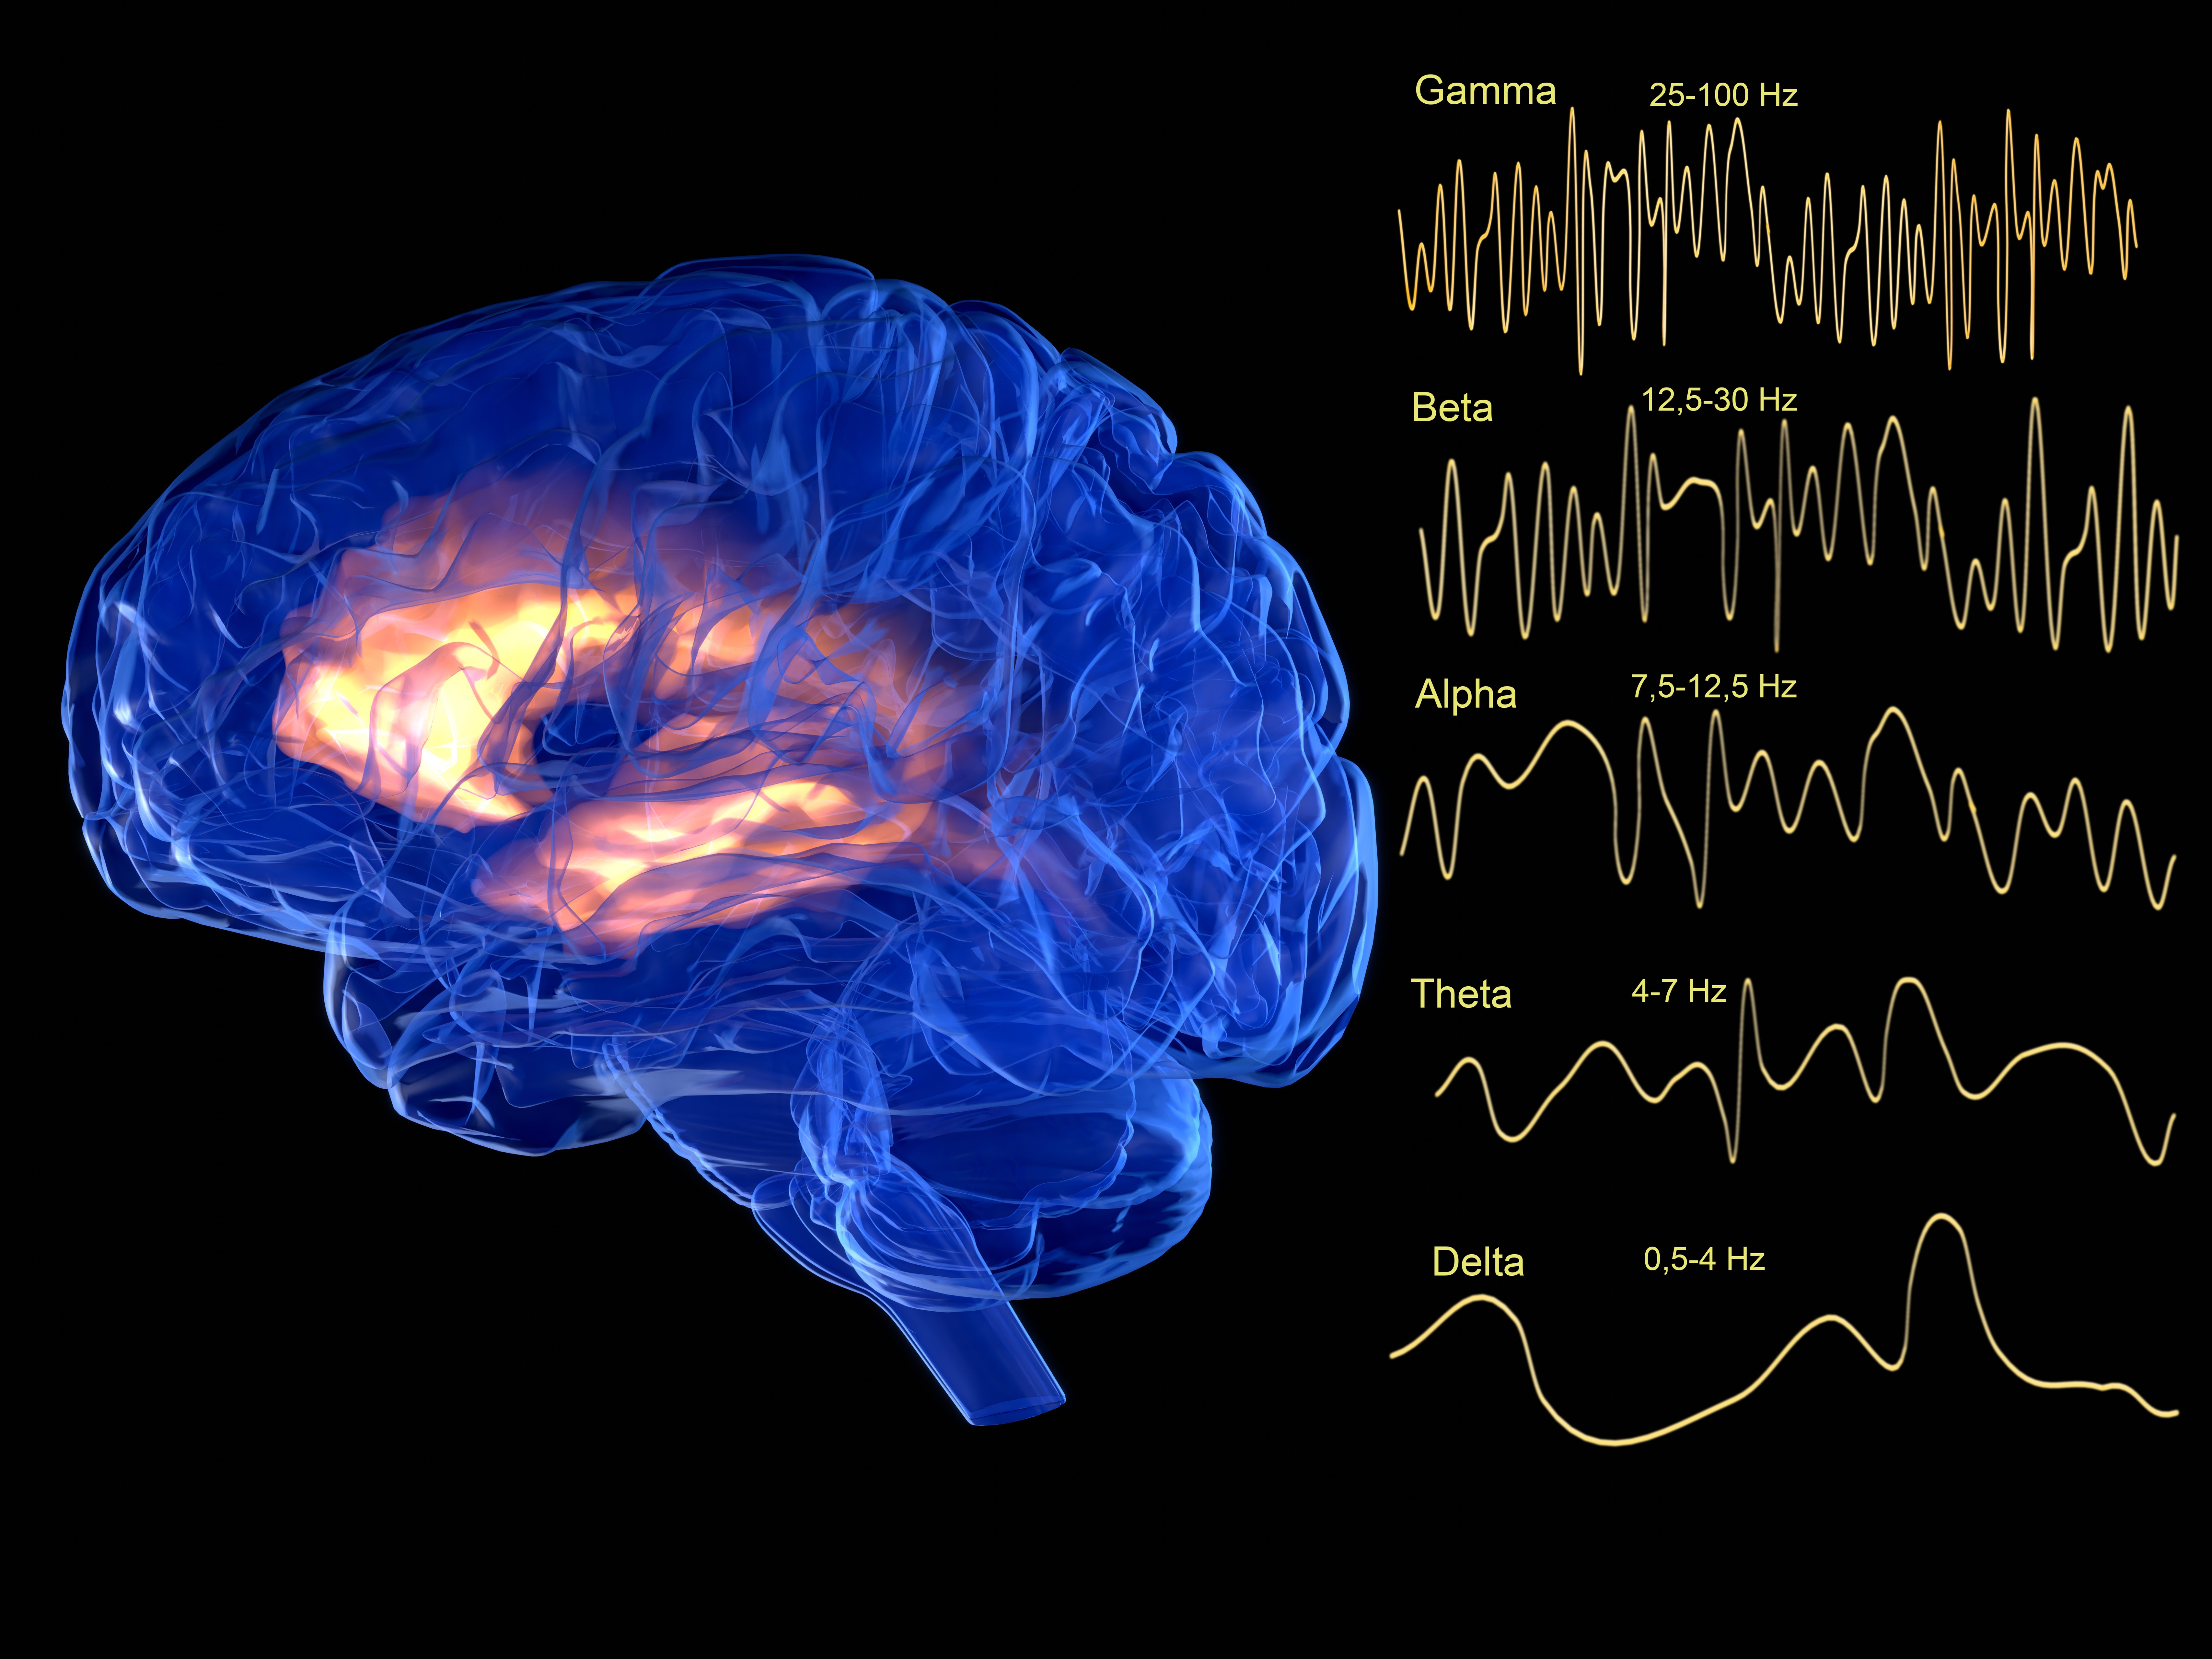

These are the best, creepiest, weirdest facts I have ever learned. "There's the part of your brain that recognizes faces, and the part that stores memories and feelings associated with a person. In a normally functioning brain, when you see a person you recognize, your brain looks up the feelings associated with that person. In Capgras, that process fails, so when you see someone you know and love, you get this strong sense that it just doesn't feel like that person. So your brain reconciles that disconnect by concluding that the person must be an imposter or duplicate. You can imagine the paranoia it would lead to if suddenly every important person in your life felt off, and you thought everyone was an alien clone or something." "So what the scientific community says, which makes reasonable sense, is that when the brain realizes when the heart stops, and oxygen levels plummet fast, the brain uses all of its last energy to look through all of its memories to try to make sense of this unprecedented catastrophic thing that’s happening to it." "When I had my near-death experience, I had the 'life flashing before my eyes' thing, but it wasn't like a video on fast-forward. It was a single emotional impression of the sum total of all my actions in life. It was pretty terrifying and caused me to change how I lived." "If that isn't enough to creep you out, the environment of the bog keeps much of their body preserved; hair, skin, and organs all kept intact, so the bodies have retained much of their original human form except for their bones. Which are dissolved. Look up pictures of a bog body; they are so fascinating. Creepy, too. Forensic anthropologists have even discovered remnants of a last meal in several of these bodies. I guess vegetable porridge and gruel were popular back in the day." "When we had the first countrywide outbreak here, my brother, who was dating a beef farmer, came home one day white as a sheet. He said he had just watched a cow literally break dance in front of him, then drop down and die. He was freaked out that something that big could move like that and then die in front of him. I doubt it was head spins, but I guess you try to describe something you have never seen before." Please note: some comments have been edited for length and/or clarity.